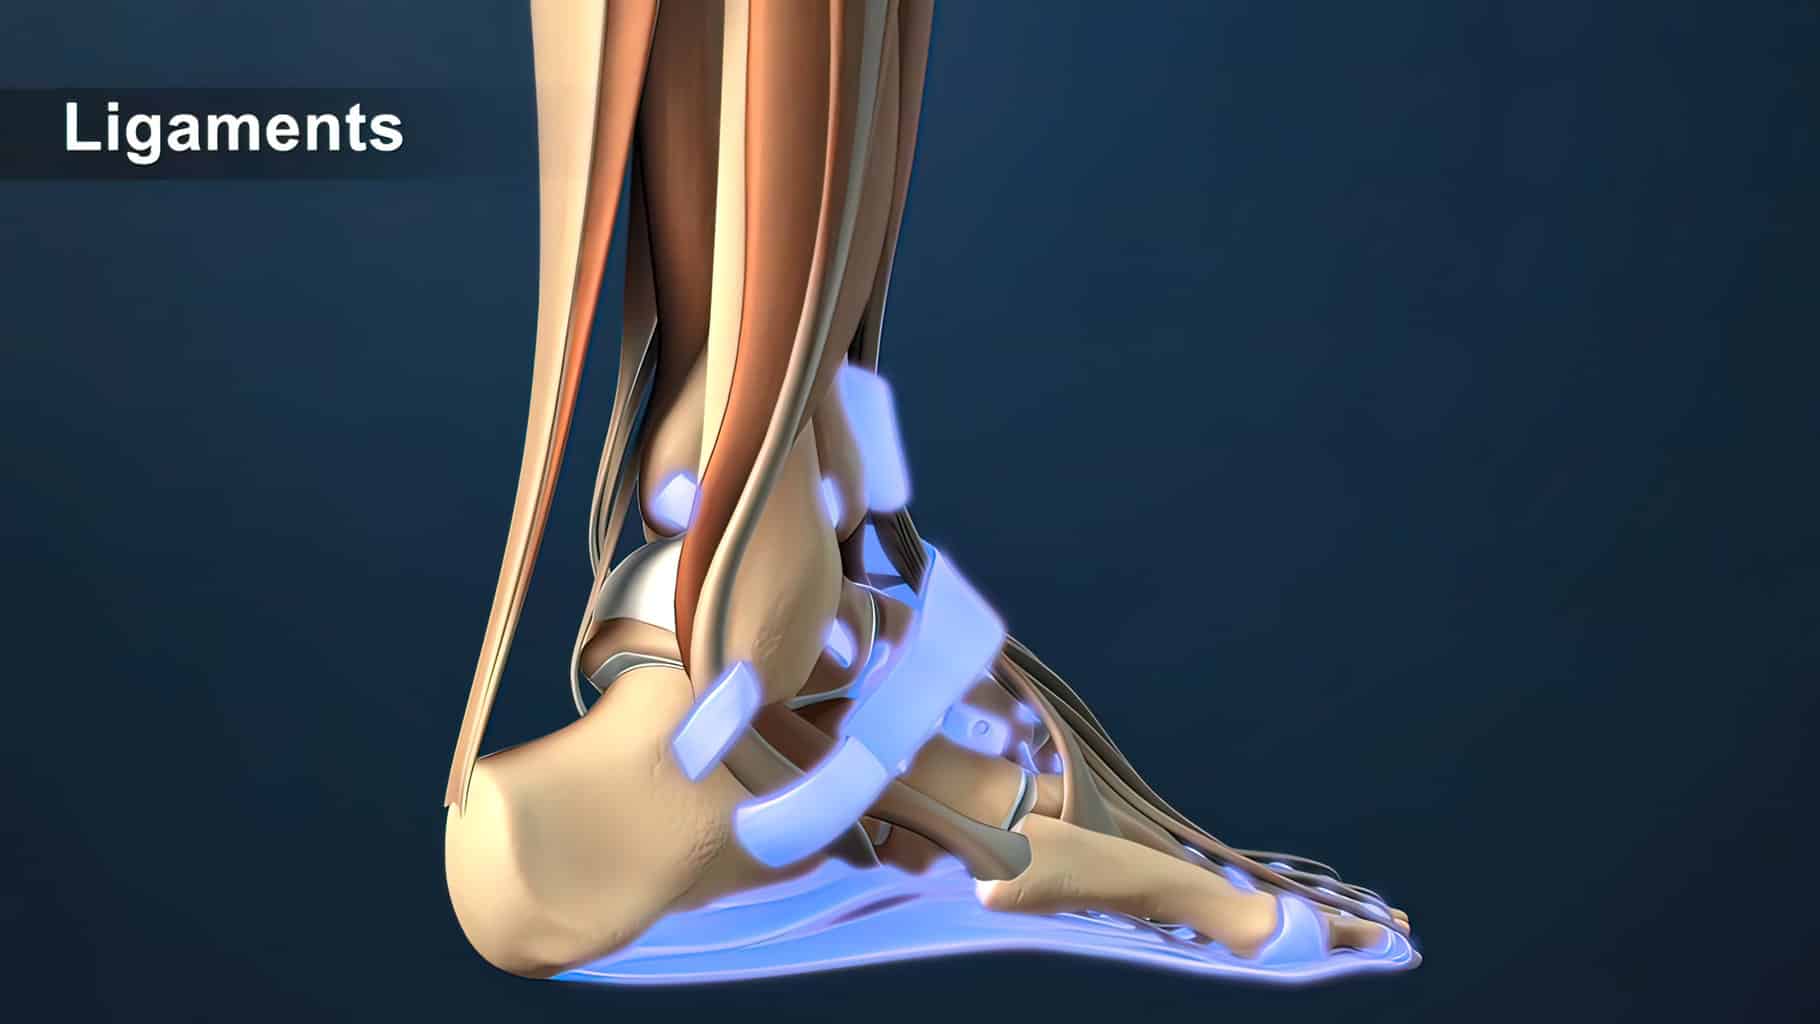

In addition to the information above, here is a curated collection of images related to Ligaments Meaning Types Functions Anatomy Example More.

- Ligaments Diagram | Quizlet